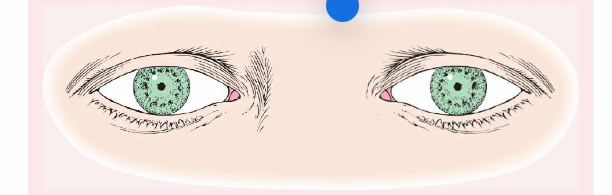

Pseudostrabismus

Normal in young children, the pupils will appear at the inner canthus (due to the epicanthic fold).

Strabismus (or Tropia)

A constant malalignment of the eye axis, is defined according to the direction toward which the eye drifts and may cause amblyopia.

Esotropia

(eye turns inward).

Exotropia

(eye turns outward).

Phoria (Mild Weakness)

Noticeable only with the cover test, is less likely to cause amblyopia than strabismus.

Esophoria

is an inward drift and

exophoria

an outward drift of the eye.